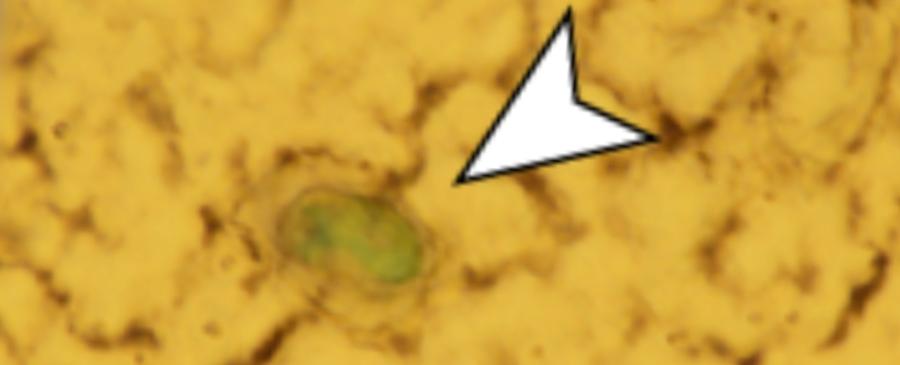

Международен екип от учени изследва обонятелните луковици - масиви от мозъчна тъкан, които приемат информация за миризмите от носа - на 15 починали хора и открива наличието на микропластмаса в 8 от тях.

Изследователите отбелязват, че най-разпространените форми са частици и влакна, а най-разпространеният полимер е полипропиленът: това е една от най-широко използваните пластмаси, която се среща във всичко - от опаковки до автомобилни части и медицински изделия. Размерите на частиците варират от 5,5 до 26,4 микрометра, което е не повече от една четвърт от ширината на средния човешки косъм.

Предишни изследвания установяват, че мръсните частици във въздуха навлизат в тялото ни през обонятелните пътища - последното проучване показва, че микропластмасата също може да ги използва, за да достигне до мозъка (по-специално – тя се вмъква в малки дупчици в крибриформената плочка (точно под обонятелната луковица)).